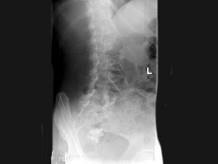

问题 女,47岁,腰背痛并向髋部和下肢放射,结合图像,最可能的诊断是?(?)

选项 A.腰5压缩性骨折 B.移行椎 C.脊椎裂 D.腰5椎弓峡部不连 E.Klipple-Feil综合征

答案 D